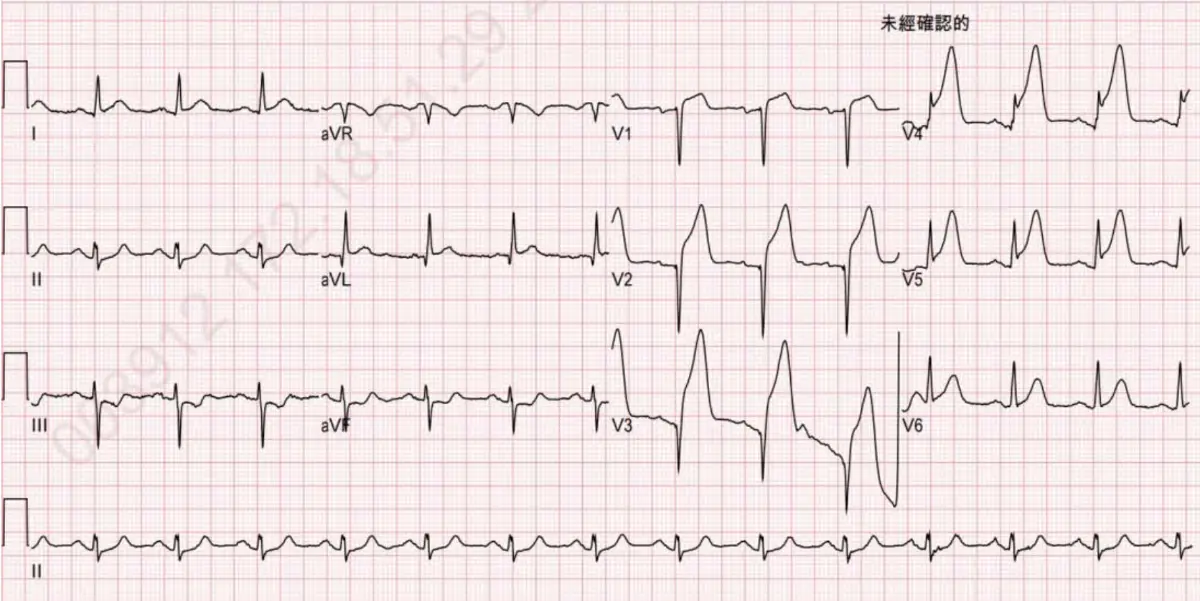

承上題【一位70歲女性病患胸痛1小時到急診,過去病史有高血壓與高血糖;但血壓控制不良,至急診時血壓為160/100毫米汞柱,糖化血色素最近數值為8.0%,最近無出血傾向或上消化出血紀錄,血氧飽和濃度(SpO₂) 為98%.聽診心臟無S3奔馬音,肺部聽診無濕囉音(moist rales)或喘鳴音(wheezing),四肢皮膚溫暖且下肢無水腫,心電圖與胸部X光片如圖一及圖二。請問下列敘述何者為是? 】,該名病患於出院後3個月心臟超音波左心室射出分率 (LVEF)為25%,血清肌酐酸為1.1 mg/dl,血清電解質無異常,爬一層樓梯不到便會發生胸悶跟動喘,在2週後發生到院前喪失生命徵狀(out of hospital cardiac arrest),經送至急診回復生命跡象與意識,住院後做了心臟核磁共振掃描(late gadolinium enhancement)如附圖。有關這位病人的處理,下列何者不正確?

- 心電圖:V1–V4明顯出現pathological Q波及R波消失,並可見T波倒置,顯示曾有前壁心肌梗塞的痕跡,符合左前降支區域心肌壞死後的「Q波」表現。